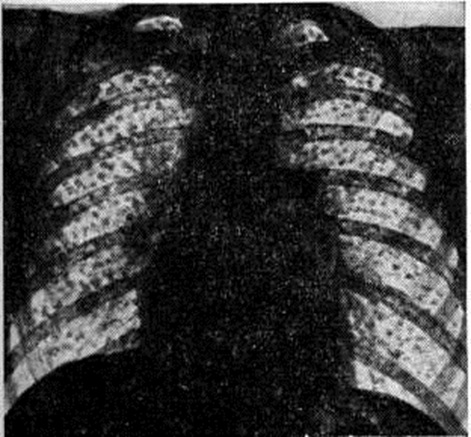

Определённая роль отводится индивидуальной предрасположенности, возможно связанной с генетическими особенностями организма, в том числе и иммунного гомеостаза. Патологическая анатомия. Силикоз характеризуется развитием специфических прогрессирующих клеточно-пылевых и фиброзных силикотических узелков в лёгких и регионарных лимфатических, узлах на фоне диффузных интерстициальных изменений, реже в верхних дыхательных путях, трахее, бронхах, исключительно редко в других органах. Силикотический узелок в начале процесса отличается концентрическим или вихреобразным расположением аргирофильных, в дальнейшем плотных гиалинизированных коллагеновых волокон, полностью вытесняющих кониофаги. Эти узелки могут быть милиарными при диффузной форме Силикоз Группы их, сливаясь, образуют в лёгких крупные узлы плотной серо-беловатой ткани (узелковая, узловая и опухолевидная формы), иногда с распадом (силикотические каверны), иногда с отложением извести в центре или по периферии узлов; узелки могут развиваться также вокруг сосудов, сдавливая их. На сподограммах (смотри полный свод знаний) или в косо падающем свете тёмного поля микроскопа в силикотических узелках, особенно по периферии, обнаруживаются светящиеся кварцевые пылинки. При Силикоз, как правило, развиваются слипчивый плеврит, хронический преимущественно атрофический бронхит, диффузный интерстициальный пневмосклероз (смотри полный свод знаний), эмфизема лёгких (смотри полный свод знаний). Больные погибают от сердечно-лёгочной недостаточности при лёгочном сердце и мускатной печени или от присоединившегося туберкулёза. Клиническая картина. В 1930 год на 1 Международной конференции по силикозу в Йоханнесбурге была принята классификация Силикоз, учитывающая как рентгенологическое данные, так и клинические, симптоматику. Эта классификация получила широкое признание в ряде стран. В последующих международных классификациях учитываются и детализируются преимущественно рентгенологические (скиалогические) признаки заболевания (характер и плотность затемнений на рентгеновском снимке). В классификациях, принятых в СССР для всех пневмокониозов, в том числе и для Силикоз (1958 и 1976), учитывались, наряду с рентгенологическими клинические, признаки болезни. Последняя и ныне действующая классификация предусматривает три стадии (I, II, III) и три формы Силикоз (узелковую, интерстициальную и узловую). Узелковая форма Силикоз (рисунок 1) характеризуется наличием в лёгких мелких округлых чётко очерченных однотипных теней. В зависимости от фазы развития узелка (клеточная, фиброзная фаза, фаза гиалиноза или кальциноза) меняется интенсивность и гомогенность узелковых теней. По величине выделяют 3 типа узелков: до 1,5 миллиметров (р), от 1,5 до 3 миллиметров (q), от 3 до 10 миллиметров (г). При интерстициальной форме Силикоз определяются усиление и деформация лёгочного рисунка, обусловленные периваскулярным и перибронхиальным фиброзом. По характеру интерстициальных изменений выделяют тонкие линейно-сетчатые изменения лёгочного рисунка (s), тяжистые, неправильные линейные тени (t), груботяжистые, неправильные, местами ячеистые мелкопятнистые затемнения (и). Линейно-тяжистые изменения наблюдаются с двух сторон, имеют диффузный распространённый характер, что наиболее выражено в средних и нижних отделах лёгких (рисунок 2). Для узловой формы Силикоз (рисунок 3) характерны фиброзные образования. По величине узловых образований различают мелкоузловой — диаметр узлов от 1 до 5 сантиметров (А), крупноузловой от 5 до 10 сантиметров (В) и массивный — более 10 сантиметров (С). Узловые образования могут быть одно или двусторонними, округлыми или неправильной формы, с чёткими и нечёткими контурами.

I стадия узелковой формы Силикоз характеризуется наличием на фоне интерстициального фиброза лёгких небольшого количества узелков (кодовое обозначение: р — 1,2; q — 1; грамм — 1), а I стадия при интерстициальной форме — умеренным двусторонним диффузным усилением лёгочного рисунка с видимыми линейно-сетчатыми и линейно-тяжистыми изменениями (s — 1,2; t — 1,2; u — 1,2). Рентгенологические признаки, определяющие переход процесса во II стадию, в основном обусловливаются усилением интерстициального и узелкового фиброза лёгких. При II стадии узелковой формы лёгочный рисунок плохо дифференцируется, видны многочисленные симметричные и равномерно расположенные мелко или средне-узелковые тени (р — 3; q — 3, грамм — 3). Силикоз II стадии при интерстициальной форме отличается большой густотой расположения линейно-сетчатых и грубо-тяжистых теней на единицу площади при более выраженном усилении и появлении деформации лёгочного рисунка (s — 3, t — 3, u — 3). Одновременно в большинстве случаев определяются также мелкие неправильной формы очажково-узелковые затемнения; III, или конечная, стадия узелкового или интерстициального Силикоз характеризуется увеличением количества фиброзных узелков, их слиянием, формированием теней массивного фиброза (А, В, С). Больные Силикоз, как правило, предъявляют мало жалоб. Чаще всего они отмечают умеренную одышку, кашель (сухой и с мокротой) и боль в груди. Клинические, проявления Силикоз нарастают по мере развития фиброзного процесса в лёгких, но полный параллелизм с рентгенологическое картиной отсутствует. Кашель и одышка при Силикоз могут быть связаны не только с выраженностью фиброза, но зависят также и от степени сопутствующего силикозу бронхита (смотри полный свод знаний), который носит преимущественно атрофический характер. Общее состояние больных довольно долго может оставаться удовлетворительным. Грудная клетка чаще обычной формы, но по мере нарастания эмфиземы лёгких расширяется с увеличением её переднезадних размеров. Типично жёсткое дыхание, иногда выслушиваются непостоянные сухие хрипы, реже в нижних отделах мелкопузырчатые хрипы и шум трения плевры. В III стадии силикоза могут обнаруживаться участки укорочения перкуторного звука и жёсткого дыхания бронхиального оттенка. По мере прогрессирования болезни может развиваться картина лёгочного сердца (смотри полный свод знаний). Клинические, анализ крови при Силикоз чаще без особых отклонений. Из биохимический исследований наибольшее значение имеет анализ крови на белковые фракции; прогрессирование Силикоз может сопровождаться гипергаммаглобулинемией. Функция дыхания чаще изменена нерезко, в начале болезни возможны умеренные обструктивные нарушения, на которые по мере прогрессирования процесса обычно наслаиваются рестриктивные. Течение Силикоз прогрессирующее, при этом развитие фиброза происходит в разные сроки. Различают Силикоз медленно прогрессирующий, остающийся на одном уровне иногда десятилетиями (чаще интерстициальный); быстро прогрессирующий — ухудшение состояния может произойти за 7—8 лет и быстрее; так называемый поздний Силикоз— развивающийся спустя многие годы после имевшего место контакта с пылью. В прошлом были описаны случаи острого Силикоз при особо неблагоприятных условиях труда, когда болезнь развивалась быстро и протекала особенно злокачественно. В наст, время острый Силикоз в нашей стране не встречается. Осложнения. Течение Силикоз усугубляется при присоединении осложнений, наиболее тяжёлым из которых является туберкулёз. Силикоз, осложнённый туберкулёзом, называют силикотуберкулёзом (смотри полный свод знаний: Туберкулёз органов дыхания). К осложнениям Силикоз относят также не часто встречающиеся острые и хронический пневмонии (смотри полный свод знаний), бронхоэктазы (смотри полный свод знаний), бронхиальную астму (смотри полный свод знаний). Иммунные и аутоиммунные процессы, развивающиеся при выраженных формах Силикоз, могут привести к возникновению системных поражений типа ревматоидного артрита (смотри полный свод знаний) и других коллагенозов. Иногда в лёгких при сочетании Силикоз с ревматоидным артритом (так называемый силикоартритом) наблюдается своеобразная картина — формирование множественных округлых затемнений (смотри полный свод знаний: Каплана синдром), при этом в крови может быть обнаружен ревматоидный фактор (смотри полный свод знаний). Диагноз устанавливают на основании клинические, симптомов, проф. анамнеза и данных рентгенологическое исследования, которым принадлежит основная роль в диагностике Силикоз На рентгенограмме лёгких отражаются все анатомические элементы, характеризующие силикотический пневмофиброз. Наряду с этим для Силикоз характерно симметричное расширение и фиброзное уплотнение корней лёгких, иногда со скорлупообразным обызвествлением лимфатических, узлов и адгезивной плевральной реакцией. Дифференциальный диагноз проводят с другими пневмокониозами и легочными заболеваниями иной этиологии, сопровождающимися синдромом лёгочной диссеминации. Для дифференциальной диагностики Силикоз особенно важны общий и проф. анамнез и гигиенические характеристика условий труда. При дифференциальной диагностике с диссеминированным туберкулёзом (смотри полный свод знаний: Туберкулёз органов дыхания), саркоидозом (смотри полный свод знаний), синдромом Хаммена — Рича (смотри полный свод знаний: Хаммена — Рича синдром) учитывают особенности течения каждой из этих форм, их клинико-рентгенологические формы, отсутствие типичного проф. анамнеза. В случаях, трудных в диагностическом отношении, можно рекомендовать диагностическую бронхоскопию с трансбронхиальной биопсией. Лечение должно быть комплексным, направлением на улучшение общего состояния организма, предупреждение осложнений и прогрессирования заболеваний. Показаны полноценное питание с достаточным содержанием витаминов, дыхательная гимнастика, лечение в санаториях и профилакториях. На ранних стадиях Силикоз используются физиотерапевтические методы: ионофорез с новокаином, хлористым кальцием, реже УВЧ на грудную клетку, ультразвук. По показаниям назначают бронхолитические препараты (эуфиллин, эфедрин и другие) сердечные средства, кислородную терапию. При сопровождающих Силикоз выраженных иммунно-патологических проявлениях допустимо осторожное назначение малых доз глюкокортикоидов под защитой антибиотиков, реже назначают делагил, плаквинил. В настоящее время изучается вопрос о возможности применения при Силикоз некоторых полимерных препаратов. Важно своевременное лечение осложнений силикоза и прежде всего силикотуберкулёза. При этом основным методом лечения является химиотерапия современными противотуберкулёзными препаратами (смотри полный свод знаний: Туберкулёз). В отдельных случаях показано хирургическое вмешательство. Экспертиза трудоспособности. Больных Силикоз переводят на другую работу, не сопровождающуюся воздействием пыли, раздражающих и токсических веществ, а также неблагоприятных метеорологических факторов; им противопоказан тяжёлый физический труд. В случае потери трудоспособности больным устанавливается проф. инвалидность. Профилактика состоит прежде всего в проведении гигиенических и медицинский мероприятий, направленных на уменьшение пылеобразования и защиту дыхательных путей от пыли (смотри полный свод знаний: Пневмокониозы, профилактика; Профилактика первичная). Проводятся предварительные и периодические медицинские осмотры, организуются группы здоровья и занятия лечебный физкультурой, показаны профилактические влажные и соляно-щелочные ингаляции и пребывание в профилакториях. В целях вторичной профилактики необходим перевод больного в условия труда, исключающие контакт с пылью. Прогноз. При отсутствии опасных для жизни осложнений и при переводе рабочего на производственные участки, свободные от пыли, прогрессирование процесса при преобладании интерстициальных изменений может приостановиться, однако сохраняется повышенный риск развития воспалительных и специфических поражений лёгких. Узелковая форма Силикоз нередко прогрессирует и после прекращения контакта рабочего с пылью. Умирают больные Силикоз чаще всего от пневмонии, сердечно-сосудистой недостаточности или от туберкулёза.